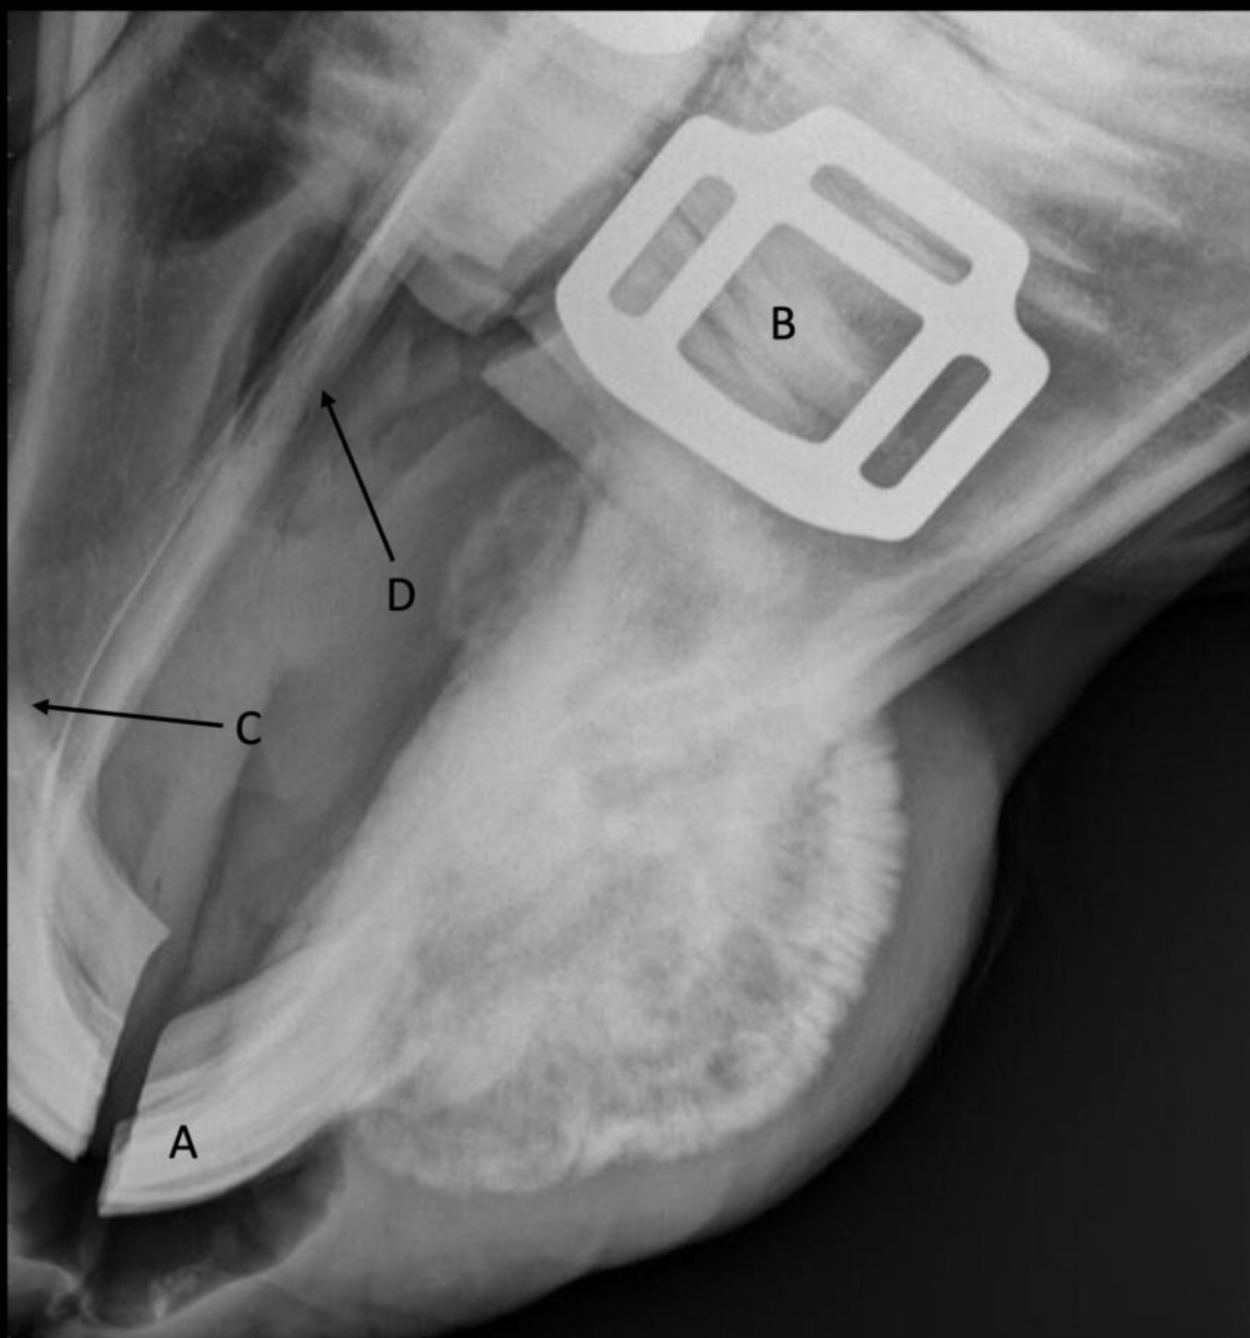

Label the structures

A

A = patella

B = distal femur

C = fabellae

D = tibia

E = fibula

A = patellar tendon

B = menisci

C = infrapatellar fat pad

D = gastrocnemius m.

E = popliteal lymph node